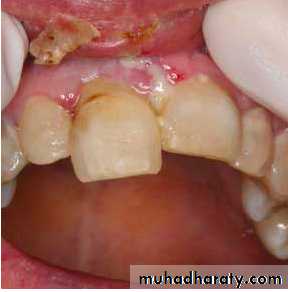

Associated injuries-Fracture of alveolar socket wall

- Injuries to the lips and gingiva